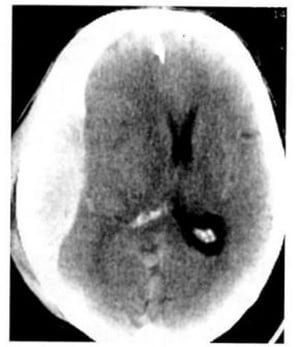

1.2. U nguyên bào đệm đa dạng (Hình 1.32)

Dấu hiệu XQCLĐT:

– U ở chất trắng trên lều, với đặc trưng là hoại tử, xuất huyết, phù nguồn gốc mạch máu, hiệu ứng choán chỗ, không đồng nhất, bắt chất cản quang đáng kể.

Hình 1.32. U nguyên bào đệm đa dạng. Hình ảnh trước tiêm (a) là tổn thương mật độ thấp ở hai bên đường giữa. Ở thùy trán bên trái còn có một tổn thương mật độ cao (xuất huyết). Sau tiêm (b), bắt chất cản quang mạnh, dạng viền.